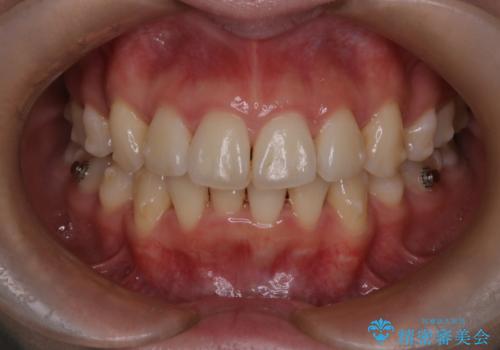

- 前歯が出ていることと、下の歯のがたがたで歯磨きがしにくいことを主訴に来院されました。

マウスピース矯正の希望があり、ワイヤーリカバリの可能性を伝えたうえでインビザライン抜歯矯正を行っています。

来院が途中途絶えたこともあり、4年ぐらい期間がかかりましたが、インビザラインだけで治療を終えることができました。